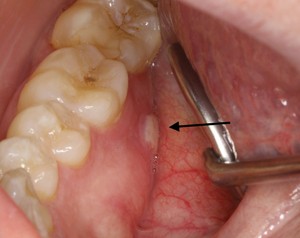

Ide o stav, pri ktorom sa kosť v oblasti čeľuste nedokáže správne hojiť a postupne odumiera. Môže sa prejaviť:

- bolesťou

- opuchom

- nehojacou sa ranou

- obnaženou kosťou v ústach